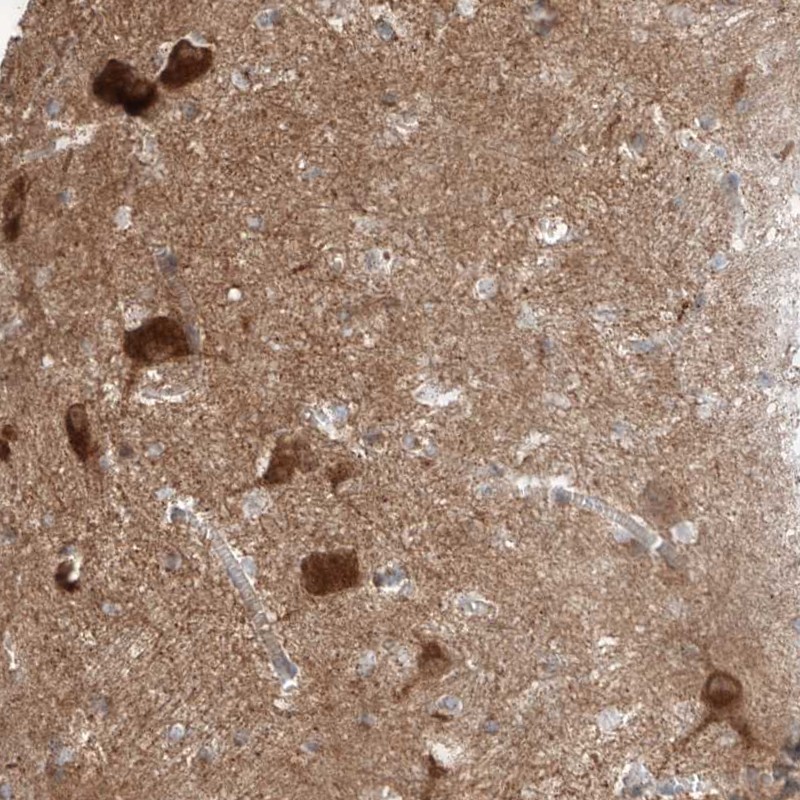

Immunohistochemical staining of human caudate shows strong positivity in neuronal cells.